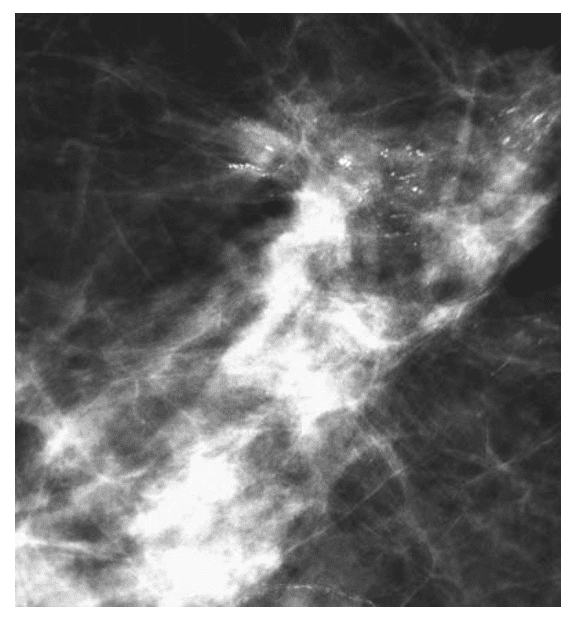

Spikulirane promene na mamografiji

Većina karcinoma dojke vizualizuje se kao stelatna senka, mada takav prikaz mogu imati i benigne lezije (postoperativni i radiacioni ožiljak, masna nekroza). Pojedinačne spikule su prave i visokog intenziteta. Sastavljene delimično od kolagena, te se lako uočavaju u lipomatoznim dojkama, dok kod žlezdane građe dojke, ne moraju biti uočljive. Spikule se šire od centra promene i njihova dužina zavisi od veličine tumora. U slučaju nemogućnosti razlikovanja benignih od malignih promena, potrebno je uraditi biopsiju.